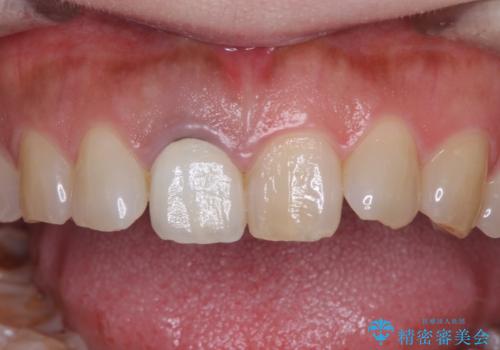

- セラミッククラウンが白すぎる前歯と、放置している奥歯を気にして来院された患者様です。

前歯のセラミッククラウンは将来ホワイトニングをするつもりで白くしたものの、それほど白くならず、ホワイトニングも面倒くさいとのことで白すぎる印象となっていました。

奥歯は虫歯が放置されていましたが、特に症状はなく歯髄の状態も正常でした。

前歯、奥歯ともにオールセラミッククラウンやセラミックインレーにて治療を行うこととしました。

前歯のセラミッククラウンは周りの歯と調和させるためにオーダーメイドタイプのものをおすすめしましたが、元が白すぎていたため、概ね色合いが合えば大丈夫であるとのことで、既製パターンの色調で仕上げました。